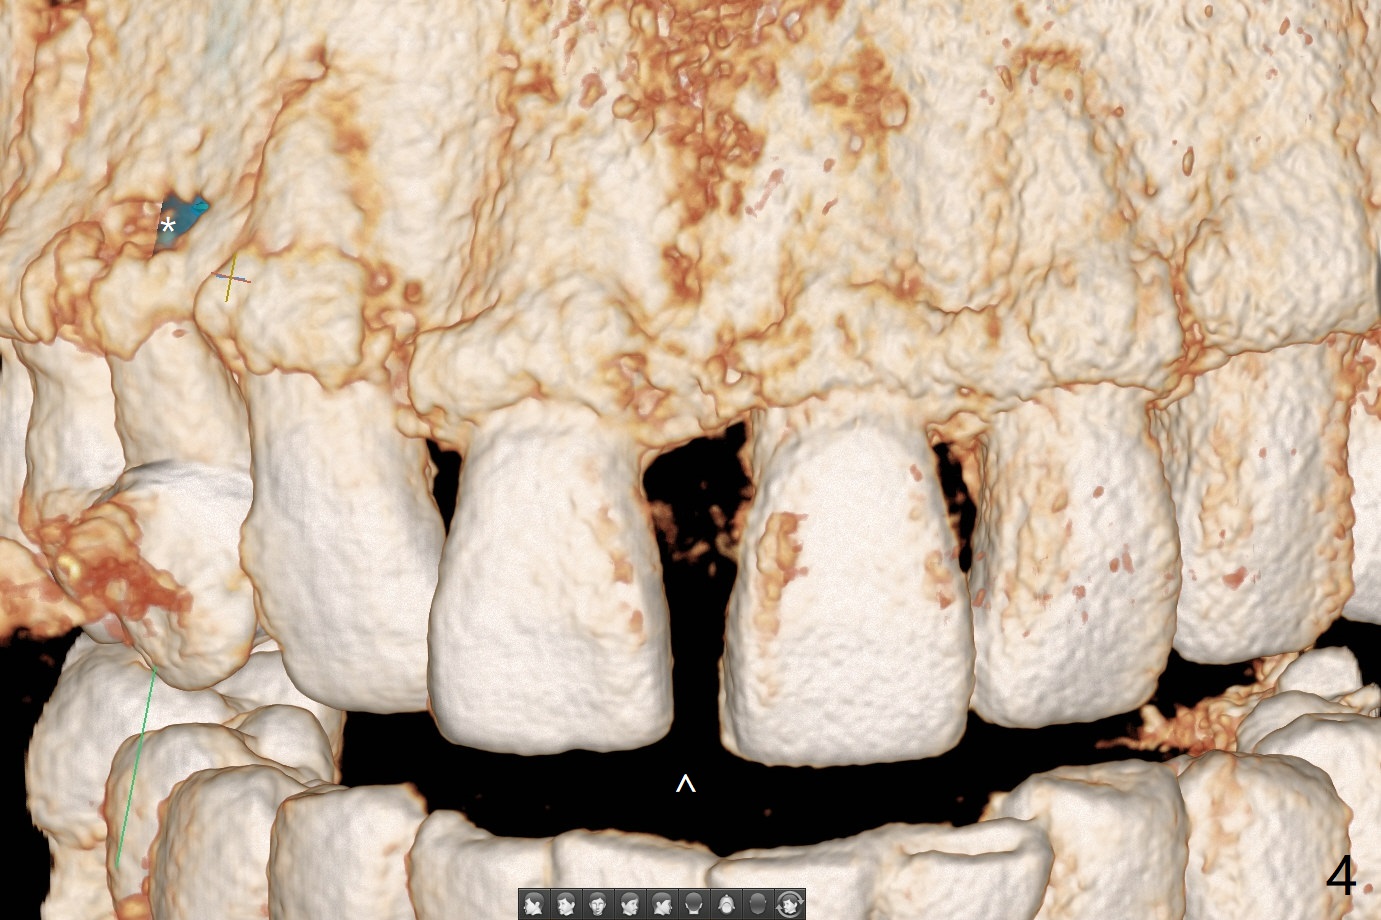

A 52-year-old man requests extraction of the mobile deciduous canine for implant (Fig.1). Use sticky bone (Fig.2 red) to maintain the canine prominence (>). In fact, there is apical perforation of the deciduous canine (Fig.3-5: *). Before bone graft, place a small piece of PRF for repair. The patient refuses to close the diastema between #8 and 9 (Fig.4 ^). Since the cancellous bone is 2.9 mm (Fig.3), it is safe to place a narrow implant (Fig.7). Return to Protect Graft Clindamycin 手术 15 Xin Wei, DDS, PhD, MS 1st edition 04/28/2021, last revision 05/27/2021